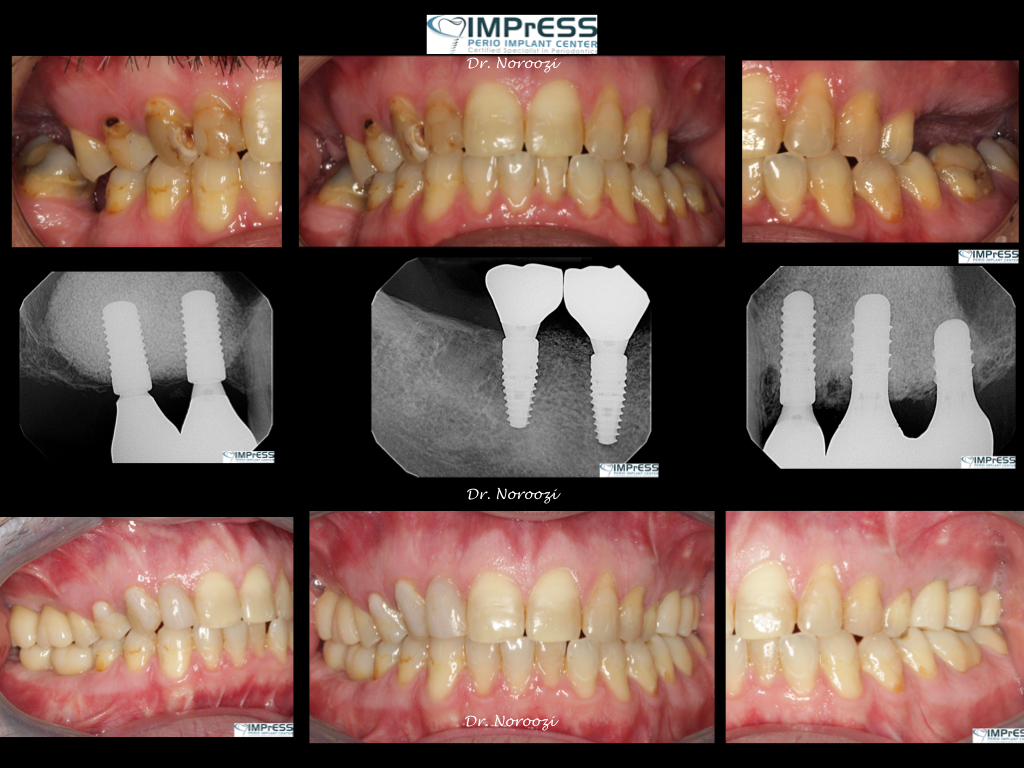

Before & Afters of Dental Implant Patients

Complete Dental Implant Cases Gallery

General Disclaimer: The results in the photographs are examples only and do not imply any certainty of the result of a procedure, and all outcomes are subject to the circumstances of the individual patient.